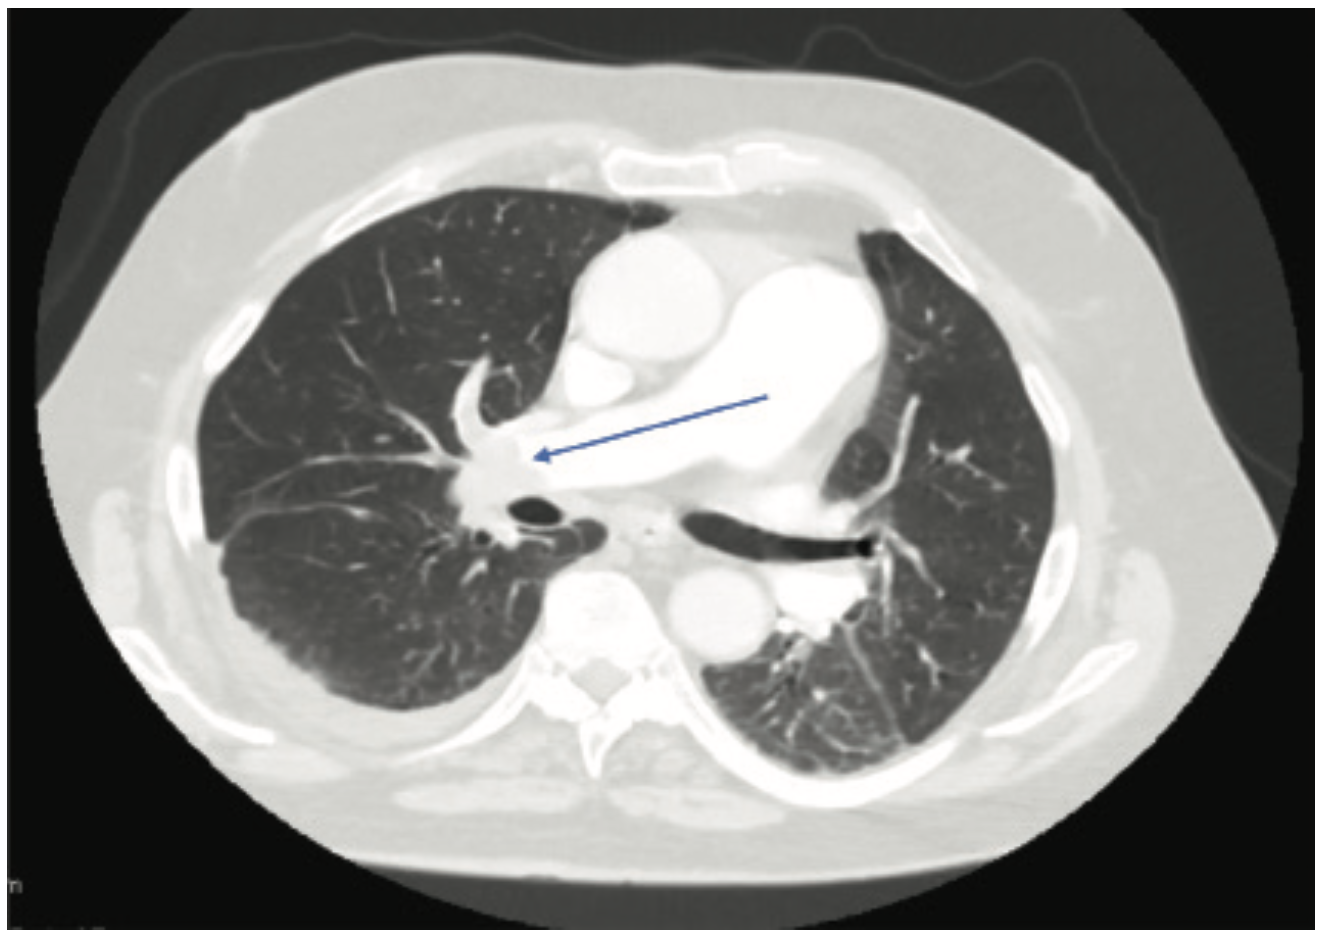

An 80-year-old male with no known past medical history presented to the emergency department at an outside facility with increasing dyspnea for the past ten days. Two weeks prior to his presentation, the patient had a fall. The patient had been immobile since then. Computed tomography (CT) angiogram of the chest showed a completely occluded right pulmonary artery and a partially occluded left pulmonary artery (Figure 1). Duplex of the lower extremity also revealed thrombosis of the left common femoral vein, femoropopliteal, and tibioperoneal veins. His BNP was also noted to be elevated at 306 pg/ml and his troponins were also elevated at 0.09 ng/ml (upper limit was 0.04 ng/ml). As he was hemodynamically stable, the patient was transferred to our facility for possible catheter-directed thrombolysis given his clinical picture of submassive pulmonary embolism. On arrival, an emergent bedside echocardiogram showed a clot in transit from the right atrium to the right ventricle (Figure 2), as well as a severely enlarged right ventricle and moderate tricuspid regurgitation. Due to the huge clot burden, right ventricular strain, and clot in transit, the patient underwent emergent surgical embolectomy. Surgery was successful in removing most of the clot with no complications. Intraoperatively, the clot was found to extend from the right atrium through the tricuspid valve into the right ventricle and all the way to the main pulmonary arteries. There was some residual thrombus in subsegmental areas that was left for medical treatment. The patient had remarkable improvement and was able to go home in a couple of days. He was discharged on rivaroxaban. On follow-up, the patient elected to have an inferior vena cava (IVC) filter placed, which was done successfully. Repeat CT angiography was done 4 months after presentation and showed resolution of the remaining thrombi. The patient continues to do clinically well on outpatient follow-up.